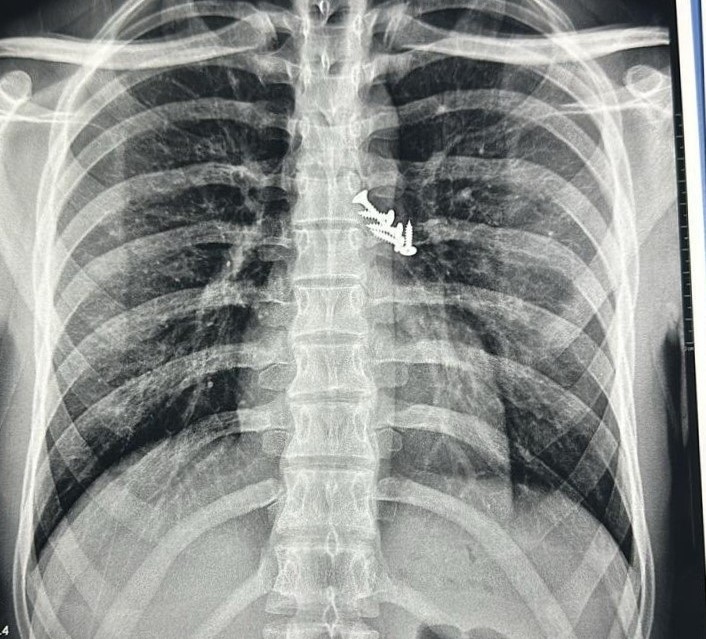

Upon regaining consciousness, the patient experienced a severe bout of coughing lasting 2-3 minutes, followed by persistent cough and chest pain. Diagnostic imaging, including a chest X-ray and plain X-ray of the abdomen, revealed the presence of five screws lodged in the lungs and two screws in the abdomen. Fortunately, screws had not caused any significant tears in the airway.

The procedure, which lasted three hours, presented significant challenges. All five screws were lodged in the left upper lobe airway and their positions were continuously shifting due to the patient’s persistent coughing, despite effective local anaesthesia. Using advanced tools, including special rat-tooth and Dormia basket forceps, the medical team successfully extracted all five screws. During the procedure, one screw slipped into the oropharynx and was swallowed by the patient. However, within 48 hours, two screws from the abdomen were naturally expelled through the faecal route.